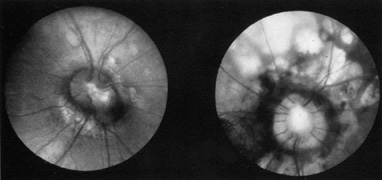

nutans. Ophthalmology 104:112, 1997 175. Gottlob IF, Zubcov AA, Wizov SS, et al: Head nodding is compensatory in spasmus nutans. Ophthalmology 99: 1024, 1992 176. Gottlob I, Wizov SS, Reinecke RD: Spasmus nutans. Invest Ophthalmol Vis Sci 36:2768, 1995 177. Wizov SS, Reinecke RD, Bocarnea M, et al: A comparative demographic and socioeconomic study of spasums nutans and

intantile nystagmus. Am J Ophthalmol 133:256, 2002 178. Gottlob I, Wizov SS, Reinecke RD: Quantitative eye and head movement recordings of retinal disease mimicking

spasmus nutans. Am J Ophthalmol 119:374, 1995 179. Lambert SR, Newman NJ: Retinal disease masquerading as spasmus nutans. Neurology 43:1607, 1993 180. Shawkat FS, Harris CM, Wilson J, et al: Eye movements in children with opsoclonus-polymyoclonus. Neuropediatrics 24:218, 1993 181. Wang PY: Acute cerebellitis with ocular flutter and truncal ataxia: a case report. Chin Med J (Engl) 50(2):169, 1992 182. De Graaf JH, Tamminga RY, Kamps WA: Paraneoplastic manifestations in children. Eur J Pediatr 153:784, 1994 183. Koh PS, Raffensperger JR, Berry S, et al: Long-term outcome in children with opsoclonus-myoclonus and ataxia and